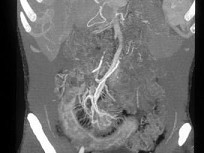

患者约30岁,结合图像,最可能的诊断为()

• A.缺血坏死性肠炎

• B.炎性腹泻

• C.克罗恩病

• D.腺癌

• E.溃疡性结肠炎